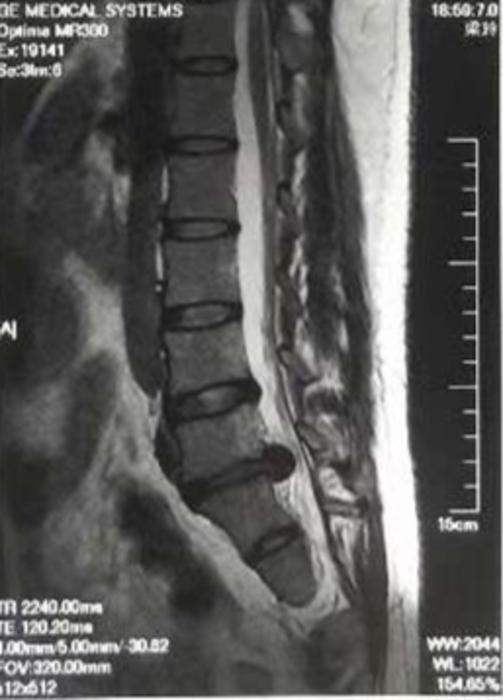

她说,一周前,起床后突然感觉腰剧烈疼痛,无法正常活动。吃了止疼药,无缓解,16日家人将其紧急送往*疆新**医科大学第六附属医院微创脊柱外科门诊,初步考虑为急性腰椎间盘突出症,进行腰椎核磁检查后确诊。

术前的脊柱图。